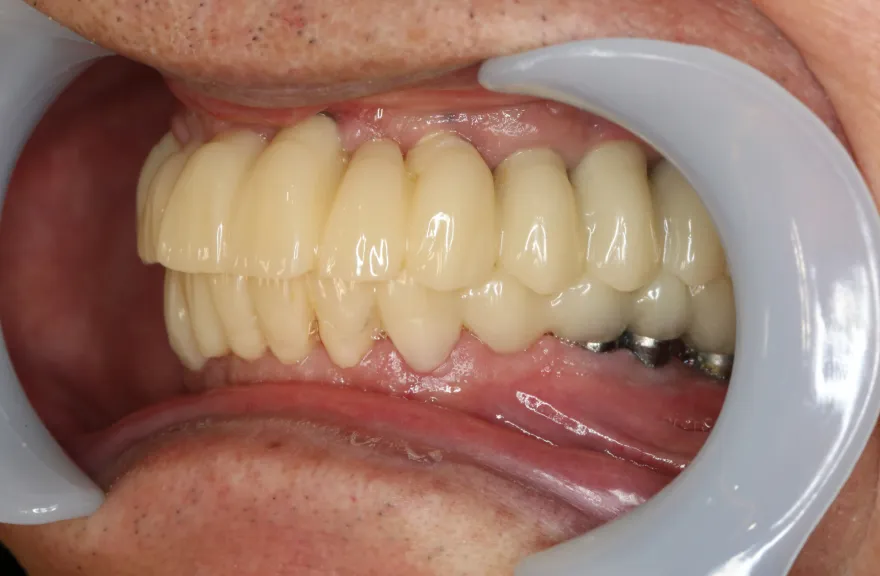

今回で完全に治療をやり切ってしまい、今後は最小限の介入で歯科と付き合えるよう、上下顎残っている歯の全ての抜歯、必要な本数のインプラント埋入、上顎は総義歯形態で対応することとしました。 - 治療のリスク

インプラント治療は決して虫歯にはなりませんしかし歯周病にはなります。

そういった方がインプラント周囲炎になる状況はあまり考えにくく定期的なメンテナンスのみしっかり行っておけば今後の人生においてトラブルを起こすことは心配しなくて良いかと考えます。

上顎の総義歯は時間と共にすり減り、劣化していきます。

10年ごと程度でやりかえが必要な可能性がありますが、虫歯治療のようにお口の中でドリルを使って削ったりする必要はなく、歯型をとって技工士へ製作を依頼するだけなので、治療の負担は限りなく小さいと言えるでしょう。